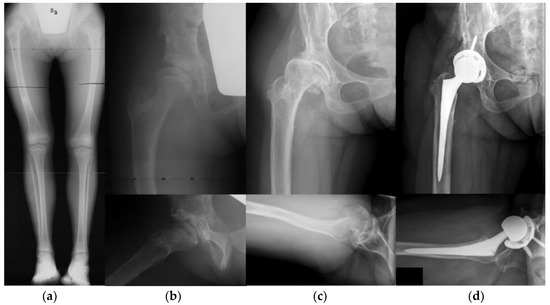

3.4. Clinical Outcomes